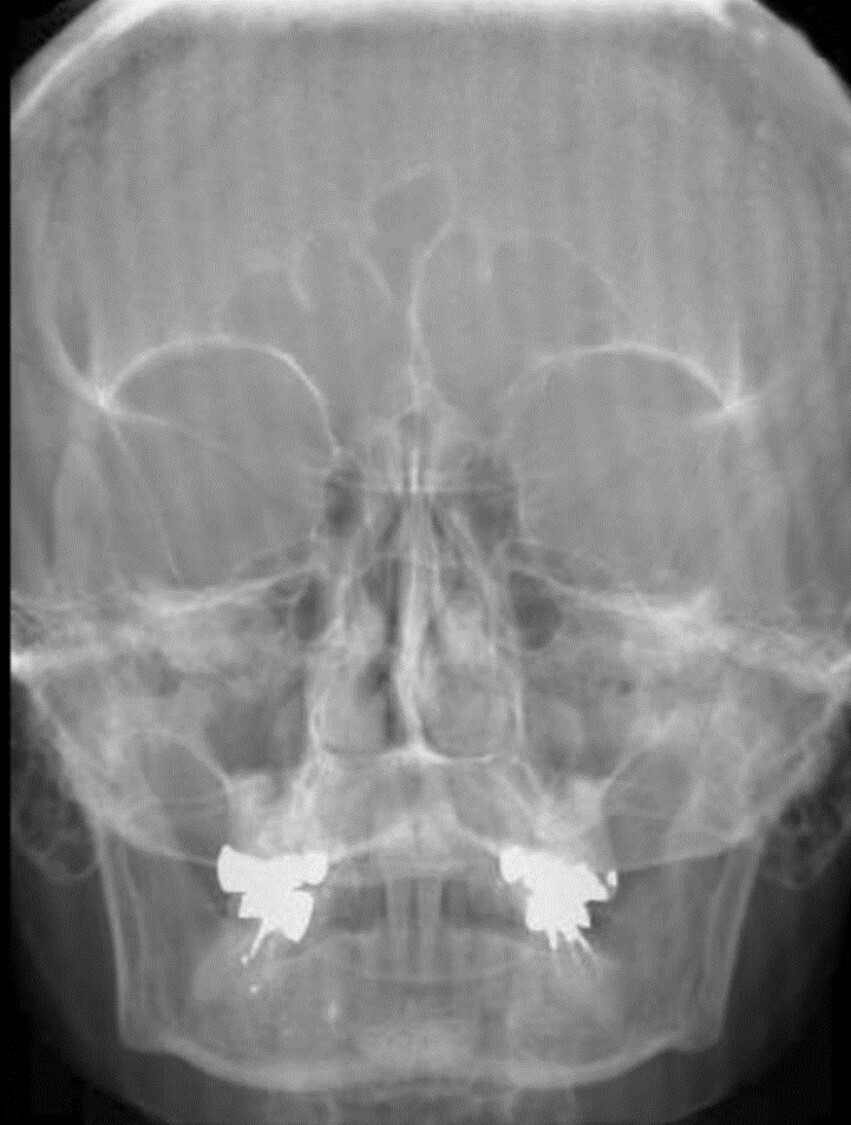

This image was acquired using the table-bucky with a grid frequency of 80lp/cm and processed with laser read out running perpendicular to the grid lines. What artifact is seen in the attached image?

A

Grid Lines